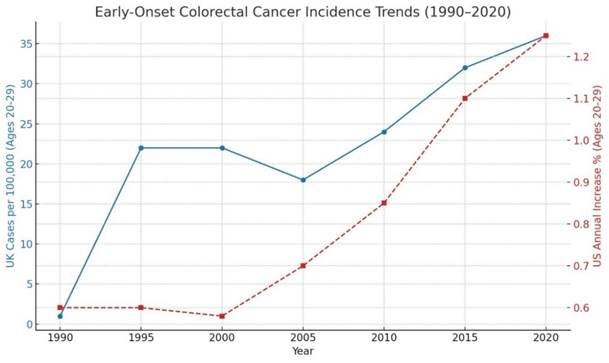

The Zigzag Theory refers to a systemic, geo-temporal distortion strategy used to fabricate the appearance of policy success while masking true causality. It involves asynchronous implementation of regulatory actions across regions, silent internal withdrawals, and selective surveillance practices that collectively distort public health data.

- Asynchronous intervention timing: Regulatory or manufacturing changes occur in one region while being delayed or omitted in another, enabling global data to be skewed in favour of intervention narratives (e.g. fortification or drug approval).

- Valproate: Regulatory action delayed in the UK compared to the U.S. and Canada. Global data pools ignored these disparities, falsely validating folic acid fortification as the driver of NTD reductions (De Wals et al., 2007). In January 2015, the MHRA issued a formal letter to healthcare professionals warning of the 30–40% risk of developmental disorders and approximately 10% risk of congenital malformations from in utero exposure to valproate, urging stricter prescribing controls and enhanced patient counselling (MHRA, 2015).

- Folic acid fortification, mandated in the United States in 1998, had already been implemented voluntarily in the UK years earlier through industry-driven practices. Early declines in neural tube defect (NTD) rates due to stricter teratogen prescribing preceded official mandates, creating a misleading illusion of policy success (Crider, Bailey and Berry, 2011).

Paramethadione: A teratogen quietly removed in Canada after its official last FDA order in 1989, making it impossible to attribute outcome shifts to known regulatory action (FDA, N.D). (See Report Section 12 – Foundational Studies).

- Although the MHRA began warning of valproate’s teratogenic risks as early as 2009, meaningful restrictions and prescribing reforms were delayed until years later (MHRA, 2009; House of Commons Health and Social Care Committee, 2021).

- FDA Delay (2013): Stronger pregnancy risk warnings issued after prescription rates had already fallen. (FDA, 2013; Baker et al., 2018)

- EMA Reclassification (2014): Required additional risk mitigation, but sales data already showed decline. (EMA, 2014; Hirst et al., 2018)

Through delaying official announcements while internally restricting high-risk drugs, regulatory bodies contributed to a misleading correlation between public intervention policies – such as folic acid fortification – and reduced neural tube defect (NTD) rates (Crider, Bailey and Berry, 2011; House of Commons, 2021). This artificial association bolstered narratives supporting synthetic folic acid, despite the fact that much of the decline began prior to formal mandates. Simultaneously, pharmaceutical and public health actors created data distortions, allowing them to claim that NTD prevalence was declining – even as valproate-exposed pregnancies continued to show persistently high rates of defects (MHRA, 2015; Jentink et al., 2010; Martin, 2017).

This section of the report tracks the historical prevalence of neural tube defects (NTDs) across the UK, US, Italy, Japan, and Australia, cross-referencing these trends with key pharmaceutical events, drug regulations, and folic acid fortification policies. The objective is to identify whether the decline in NTDs is solely due to folic acid fortification, or whether external factors, such as the reduction of teratogenic drugs, played a more significant role.

- 1965–1997: NTD prevalence declined by 96%, dropping from 3.80 per 1,000 births in 1965 to 0.14 per 1,000 in 1997. This sharp decline has occurredbefore folic acid fortification is introduced. (McDonnell, R. et al.,1999)

- 1991–2011: Prevalence remained relatively stable, with 2011 rates like 1991. No significant further reduction was observed. (EUROCAT/BMJ, 2015).

- 2011–2021: Recent data indicates that NTD prevalence has slightly increased, contradicting expectations that folic acid fortification would further reduce cases.

NTDs declined significantly before folic acid fortification, largely due to the removal of teratogenic drugs and improved prenatal care. However, recent increases in NTD rates suggest that folic acid fortification has not led to further reductions, raising concerns about its long-term effectiveness.

A 2016 study released by Stanford Medicine and covered by Erin Digitale, titled “Less decline than expected in rate of brain, spine defects after folic acid fortification program”, claimed that folic acid fortification had reduced neural tube defects (NTDs), but that the decline had since slowed (Digitale, 2016).

While presented as a supportive assessment of fortification policy, the framing of the findings portrays a subtler bias: the study assumes, without fully substantiating, that lower folic acid levels are causatively linked to increased NTD rates – despite existing data suggesting that neural tube defects were already in decline before fortification policies were implemented. This conflation, combined with funding from both the CDC and Stanford’s Department of Paediatrics institutions heavily involved in fortification promotion – raises concerns regarding neutrality.

Analysis of publicly available CDC data (2015–2024) reveals a complex trend in neural tube defect (NTD) rates that does not align with claims of uniform decline following folic acid fortification. Instead, recent findings indicate fluctuations in prevalence, raising critical questions about data interpretation and the attribution of causality.

Before folic acid fortification (pre-1998)

- Prior to mandatory folic acid fortification, NTD rates varied significantly by region.

- Estimated spina bifida prevalence was ~5 per 10,000 births in the general population.

After folic acid fortification (1998–Present)

- Following the 1998 fortification mandate, NTD prevalence reportedly dropped by ~28%, with spina bifida rates declining to 3.5 per 10,000 births.

- However, post-2010 data suggests a slowing of decline, with some areas showing plateauing or even slightly rising trends.

The initial reduction in NTDs post-fortification suggests some benefit, but data from 2010 onwards raises questions about whether long-term trends are influenced by fortification alone. Other factors – such as improved prenatal care and reduced use of teratogenic medications – may have played a larger role than acknowledged.

- NTDs declined significantly in many countries before fortification was introduced (De Wals et al., 2007; Wald et al., 2001).

- In fortified nations, NTDs did decline post-fortification, but not to the extent predicted, and it is important to remember that correlation does not equal causation. (Best et al., 2024; Crider et al., 2011).

Recent data suggests that some countries (including the UK and US) may be seeing a plateau and increase in NTD cases, despite ongoing fortification policies (Molley et al., 2023; Greenblatt et al., 2021).

The mainstream narrative credits folic acid fortification for reducing neural tube defect (NTD) rates – but the data tells a different story. A sharp decline in NTDs occurred well before fortification policies were introduced, suggesting that the true cause of the reduction was the removal of teratogenic (toxic) drugs and environmental exposures.

The key question: If NTDs had already declined by over 90% before folic acid fortification, how can policymakers claim that fortification was responsible for the drop?

- In the UK, NTDs dropped from 3.80 per 1,000 births (1965) to 0.14 per 1,000 (1997) – before folic acid fortification was introduced (Wald et al., 2001; Botto et al., 2005).

- In the US, NTDs had been declining for decades before the 1998 fortification mandate (CDC, 1995; Williams et al., 2002).